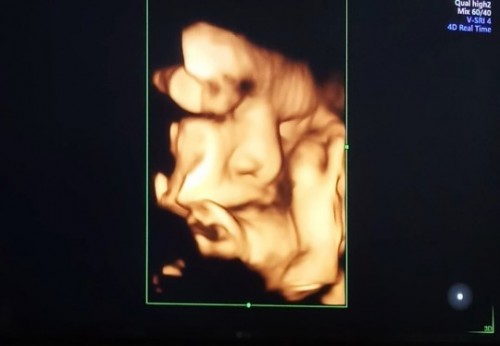

38w+2 กำหนด 4 กพ 64

จมูกพุ่งมาก อิจๆๆๆ